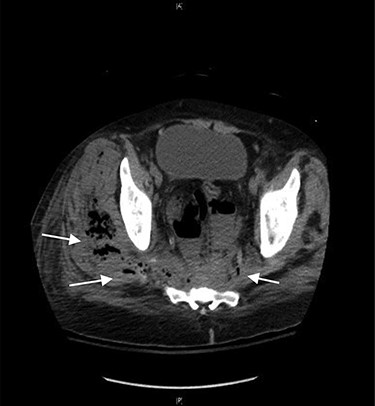

CT abdomen and pelvis showed a rectal perforation with perirectal pelvic inflammatory soft tissue/phlegmon containing air-fluid level that infiltrated into the presacral space extending up through the sciatic notch into the right gluteus medius and minimus muscle (Figs 1 and 2). Chronic inflammatory changes of the transverse colon and left colon were also present. The patient was taken to the operating room (OR) for examination under anesthesia. A flexible sigmoidoscopy was passed up into the distal descending colon, which showed discontinuous areas of ulcerated mucosa with cobble-stoning notable for active Crohn’s disease and a diffuse pseudomembrane reminiscent of C. difficile colitis (the negative C. difficle assay). A rectal perforation was noted just above the dentate line. The incision was enlarged and the presacral space was entered with a flexible sigmoidoscope. There was extensive necrosis of the presacral tissue with copious amounts of purulent fluid. The abscess was evacuated, and all loculated fluid collections were drained. The cavity was then irrigated via the sigmoidoscope. Once satisfactory drainage was achieved, a Malecot catheter was then inserted through the rectal perforation into the presacral space. A laparoscopic diverting loop ileostomy was then created to allow for healing.

CT axial view showing tract from presacral space through the sciatic notch to thigh muscles.